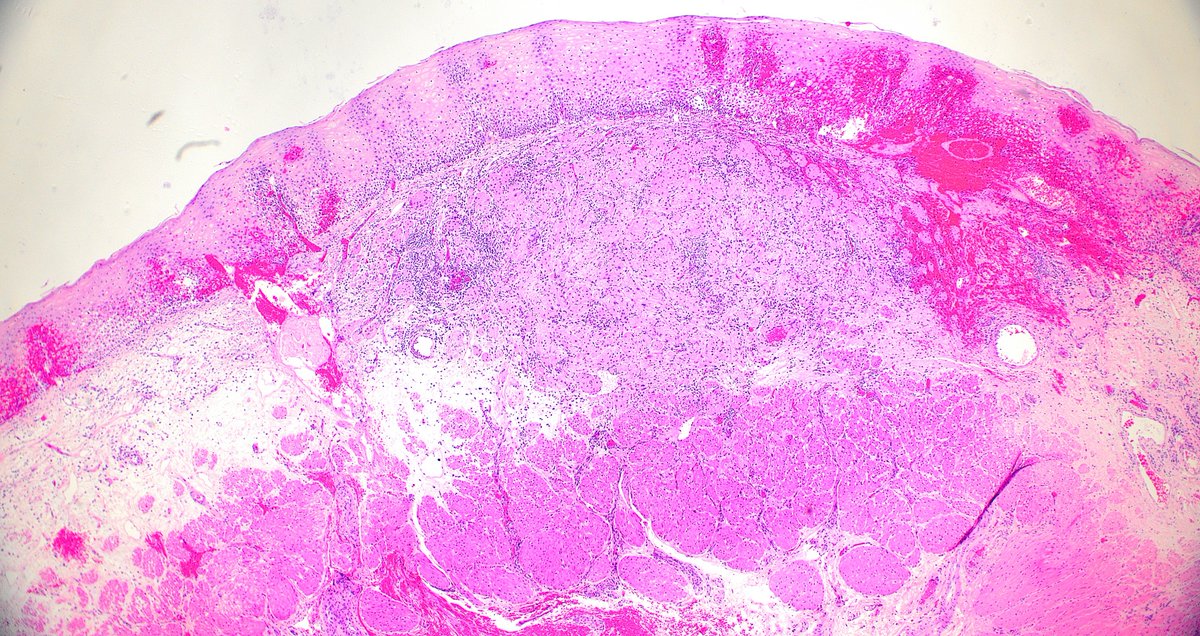

Context is everything! Radiation-associated epithelial atypia can be treacherous 😱! Learn the latest from @JBirkness (PMID: 36495943) and other incredible expert pathologists at our 25th Annual Johns Hopkins GI/Liver Pathology CME Course (virtual!) hopkinscme.cloud-cme.com/course/courseo…